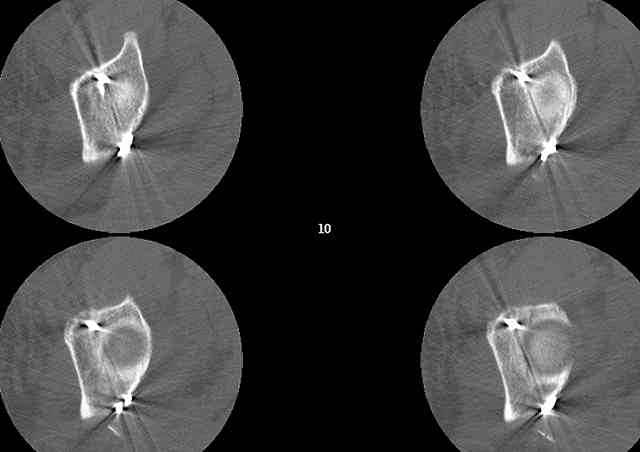

Biggest problem appears to be impaction & comminution of the posterior wall fx site - you've left out some CT cuts. This is not just fragments in joint. It may leave a deficient area, &/or block satisfactory posterior wall reduction.

May need to bone graft elevated articular fragments. Lag screws & more lateral contoured plate to buttress PW. Make sure this reduction is

anatomical.

Understand that this is no simple fracture but in the same breath is very common and can be very routinely-simplistically treated without a variety of complicated and variable scenarios...keep it simple...turn him prone, clean him up, do a nice exposure, protect the nerve, remove the debris, save it and sort it out if you can, clean the fracture lines, manipulate and clamp the transverse, hold it how you choose (I'd recommend a percutaneously inserted 3.5mm antegrade medullary lag screw), remove the clamp, reduce the

small or impacted fragments to the head, reduce the wall, and support the wall and transverse with a balanced 3.5mm contoured reconstruction plate.